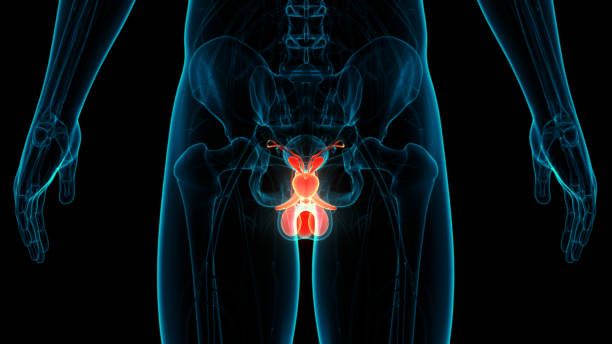

전립선은 남성 생식 기관으로 정자로 들어가는 체액을 생성하는 역할을 합니다. 이러한 전립선액은 남성 생식력에 필수적으로 샘은 방광의 목에 있는 요도를 둘러싸고 있습니다. 방광경부는 요도가 방광과 만나는 곳으로 방광과 요도는 하부 요로의 일부입니다. 전립선은 조직의 바깥층으로 둘러싸인 두 개 이상의 엽 또는 섹션을 가지고 있으며 방광 아래 직장 앞에 위치하며 요도는 방광에서 몸 밖으로 소변을 운반하는 관으로 요도는 음경을 통해 정액을 운반하는데 그 부위에 염증이 생기는 것을 전립선염이라고 합니다. 이러한 증상은 전립선 및 때로는 전립선 주변 부위의 염증과 관련된 지속적인 통증이 생기는 것을 의미하며 이번 시간에는 전립선염으로 생길 수 있는 여러 증상에 대해 정리해보겠습니다.